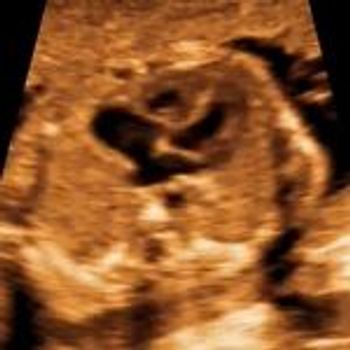

QUIZ: These images of the fetal eyes reveal a clue about the mother's health.